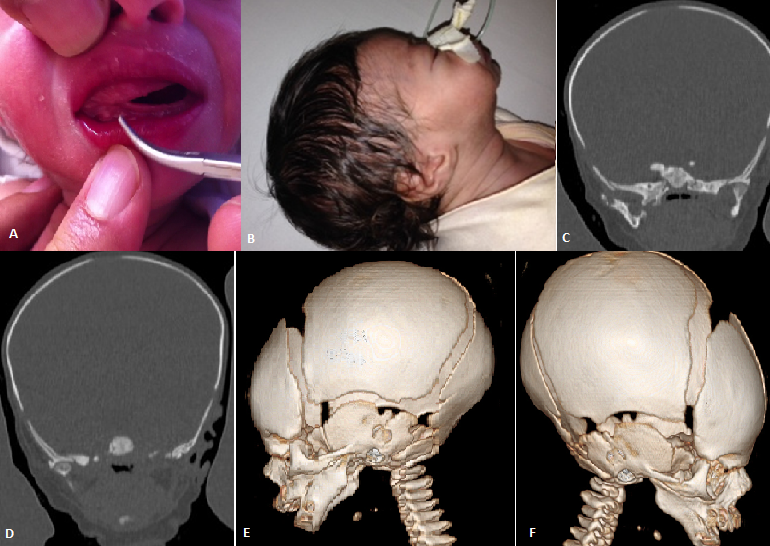

The congenital fusion of the maxilla and mandible is a rare anomaly which is usually diagnosed after birth when it is discovered that the child is unable to open his mouth. Congenital synostosis of the mandible and maxilla is even less common than synechiae, with only 25 cases reported in the literature. We report the case of a five days-old newborn. History of the disease dates back to the birth by finding limiting the opening of the oral cavity with impossibility to breastfeed. The clinical examination of the child on admission to the neonatal department reveal a reactive newborn with birth weight at 2700 g, a good sucking reflex and limited mouth opening (A) with retrognathia (B). No signs of dehydration or malnutrition. Laboratory tests found urea at 1.62 g/l, creatinine at 15 mg/l. renal ultrasound found a right kidney measuring 3.7x 1.6 cm and the left 3.5 x 1.6 cm with well differentiated without dilatation of their pelvis. Maxillary CT with 3D reconstruction revealed hypoplasia of the ascending branches of the mandible; the temporomandibular joints were normal (C,D) with bilateral Maxillomandibular Syngnathia (E,F). A gastric tube was introduced for enteral feeding; the patient gained weight. After general anesthesia; tracheotomy, we proceeded by releasing synechiae between the dental arches and osteotomy of the bone bridge by endobuccal route. A prosthesis was put in place to keep the baby mouth open. The patient was admitted to intensive care where extubation was performed at J2; post-operative follow-up was uneventful.